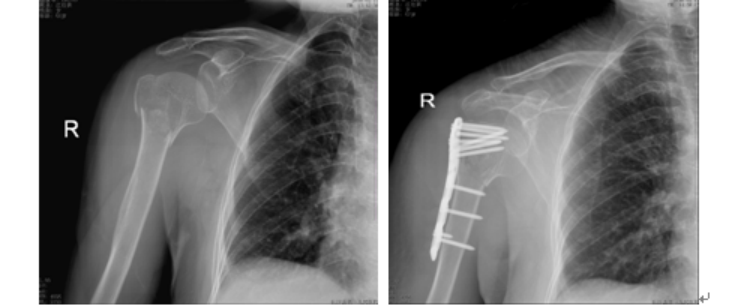

1.钢板固定

骨质疏松性骨折内固定失败常发生在内植物和骨交界处,而不是内植物自身如螺钉切和钢板移位等[6]传统钢板固定系统治疗骨质疏松性骨折时,内固定装置在组织内的把持力下降治疗效果不佳。皮质骨厚度每减少1mm,螺钉的把持力会降低50%1000N[7][8]锁定钢板传统钢板结构的主要区别在于内植物和骨折块之间应力传递的方式不同。传统钢板只有通过拧紧螺钉,增加钢板对骨的压力,从而使骨-钢板界面产生足够的摩擦力,才能维持传统钢板的稳定。但是,压力对螺钉周围骨质产生的预负荷作用会压迫骨膜,影响骨折端血液供应,增加螺钉脱出的风险。螺钉一旦开始松动,骨-钢板界面产生的摩擦力随之减少,导致钢板松动若钢板松动发生在骨折愈合前,骨折端将不能维持稳定,最终导致钢板断裂。骨质疏松性骨折本就易发生于骨干骺端,且骨质量差,传统螺钉很难维持牢固的固定,因此传统钢板用于骨质疏松性骨折的固定失败率较高。锁定钢板应力负荷的传递是通过锁定螺钉和钢板,由于锁定钢板系统的定性是依靠具有角度稳定的螺钉与钢板之间的界面维持,具有整体稳定性,除非周围的螺钉全部被拔出或发生断裂,单个螺钉很难会被拔出或断裂[9]因此选择多角度固定钢板,可增强稳定性与把持力。

但是,锁定钢板的应用仍有许多问题值得注意锁定钢板的刚度过高,导致在一定载荷下,骨折块间的微动过小,抑制骨痂形成,从而影响骨折的二期愈合,甚至骨不愈合[10]。此外,高度粉碎性骨折残的骨折块间隙或对侧皮质缺损均会增加骨折部位弯曲的风险,最终导致内固定失败。因此,在使用锁定钢板时,应尽可能减少骨折块之间的间隙[11]此外还应选用较长的锁定钢板,较少数量的螺钉和较宽的钢板跨度,以使应力分散[12]

锁定钢板在承受轴向载荷会发生微小弯曲,由此产生的骨折块间微动是不对称的,越靠近钢板侧的皮质,骨折块间微动越小,越不利于骨痂生成,最终导致骨痂形成不对称。为了克服锁定钢板的这些缺陷,近年来也出现许多新的技术,例如对侧皮质锁定技术近侧皮质开槽技术,其目的均是为了降低锁定钢板的刚度,减少因刚度过高导致的不愈合[13] [14] [15]对侧皮质锁定技术为了增加弹性和防止对侧皮质承受的应力过大,其使用的锁定螺钉直径较传统螺钉小,而可能会过早发生疲劳断裂[16]。而近侧皮质开槽技术不需要使用特制的锁定螺钉,但是近侧皮质需提前开槽。尽管这些新技术的效果已经得到了生物力学研究的证实,但是由于缺乏高级别的临床研究证据,目前其临床应用仍受到许多限制。